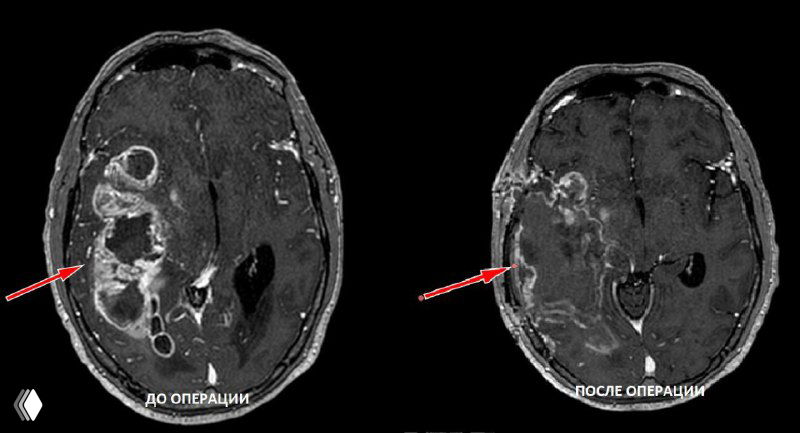

Глиобластома часто протекает скрыто и может достигать больших размеров; на снимках — опухоль, заполняющая более половины правого полушария.